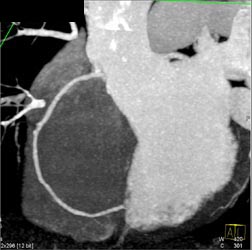

Diagnosis

Normal RCA